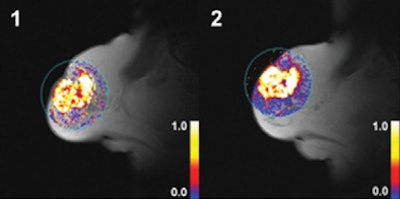

| Dynamic T1-weighted MR images of a 60-mm grade 2 breast carcinoma in the right breast of a 70-year-old woman whose disease relapsed 38.8 months after diagnosis. The patient died 47.2 months after initial radical treatment. Her tumor displayed high values for Ktrans after two cycles of chemotherapy. (1) Ktrans before treatment; (2) Ktrans after treatment. Images courtesy of Radiology. |

In addition, the researchers used the kinetic MRI parameter inflow transfer constant (Ktrans) to measure vascularity. Ktrans calculates the transfer of contrast between blood plasma and the tumor.

The researchers' univariate analysis found that the type of surgery performed and higher post-treatment Ktrans were among the significant predictors of worse disease-free survival. The same analysis concluded that clinical tumor stage and type of surgery performed were among the significant predictors of overall survival.

Patients with breast cancer "exhibiting higher levels of vascularization after two cycles of [neoadjuvant chemotherapy] experience worse disease-free and overall survival," and contrast-enhanced MRI measures of vascularity after treatment "may act as predictors of disease outcome in patients undergoing [neoadjuvant chemotherapy]," Li and colleagues concluded.